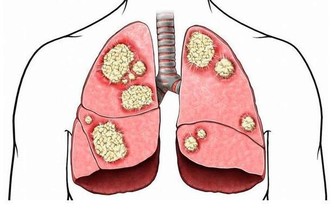

林口長庚醫院藥劑部臨床藥學科藥劑師遊佳玲指出,根據衛福部統計資料顯示,2014年國人因上呼吸道感染至門診就醫者高達585萬人。其實感冒大多由病毒引起,通常會出現咳嗽、流鼻水、打噴嚏、喉嚨痛、頭痛及全身痠痛等症狀,而市售的綜合感冒藥、感冒糖漿含有多種成分,最常見的成分是解熱鎮痛藥,對緩解感冒的咳嗽、流鼻水症狀沒有幫助。

遊佳玲藥劑師表示,服用解熱鎮痛藥容易出現腸胃不適、皮疹、水腫,甚至嗜睡等副作用,且服用過量恐造成肝腎負擔,多喝水、多休息才是治療感冒最有效的方式,大約1星期可復原;若超過2星期可能引起鼻竇炎、中耳炎,需要就醫使用抗生素治療。